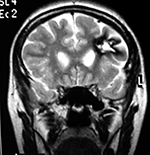

Paciente femenino de 29 años de edad con historial de cefalea crónica que presenta súbitamente disdiadococinesia y dismetría izquierda.

El estudio de RMN presenta una lesión bien circunscrita en hemisferio cerebeloso izquierdo con periferia de predominio hiperintenso en T1 y T2, y centro hipointenso, edema perilesional mínimo, así como una imagen de un vaso venoso alimentador que recorre hacia el ángulo pontocerebeloso izquierdo.

El estudio de control de RMN se observa la brecha quirúrgica y ausencia de lesión (figs. 1, 2 y 3).

Cortes axiales en ponderación T1, cambios postquirúrgicos.